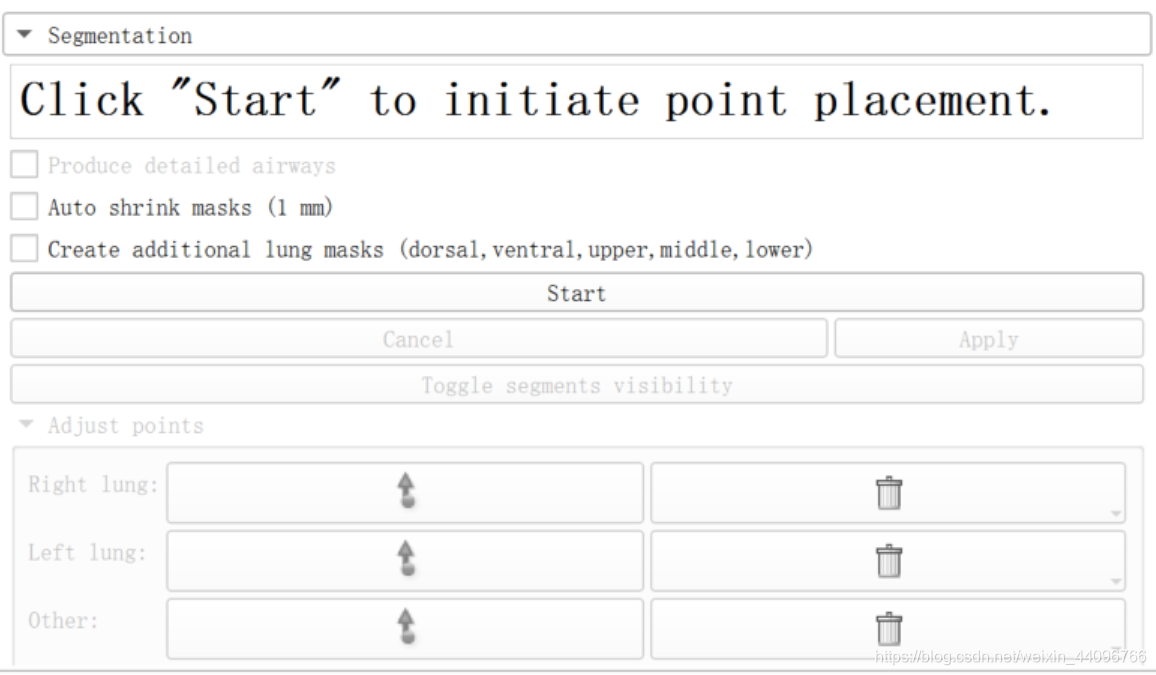

肺部分割

- 点击start,根据提示在左、右肺、气管处标点后点击apply

分割出来的区域可以根据需要在Segment Editor中手动调整。